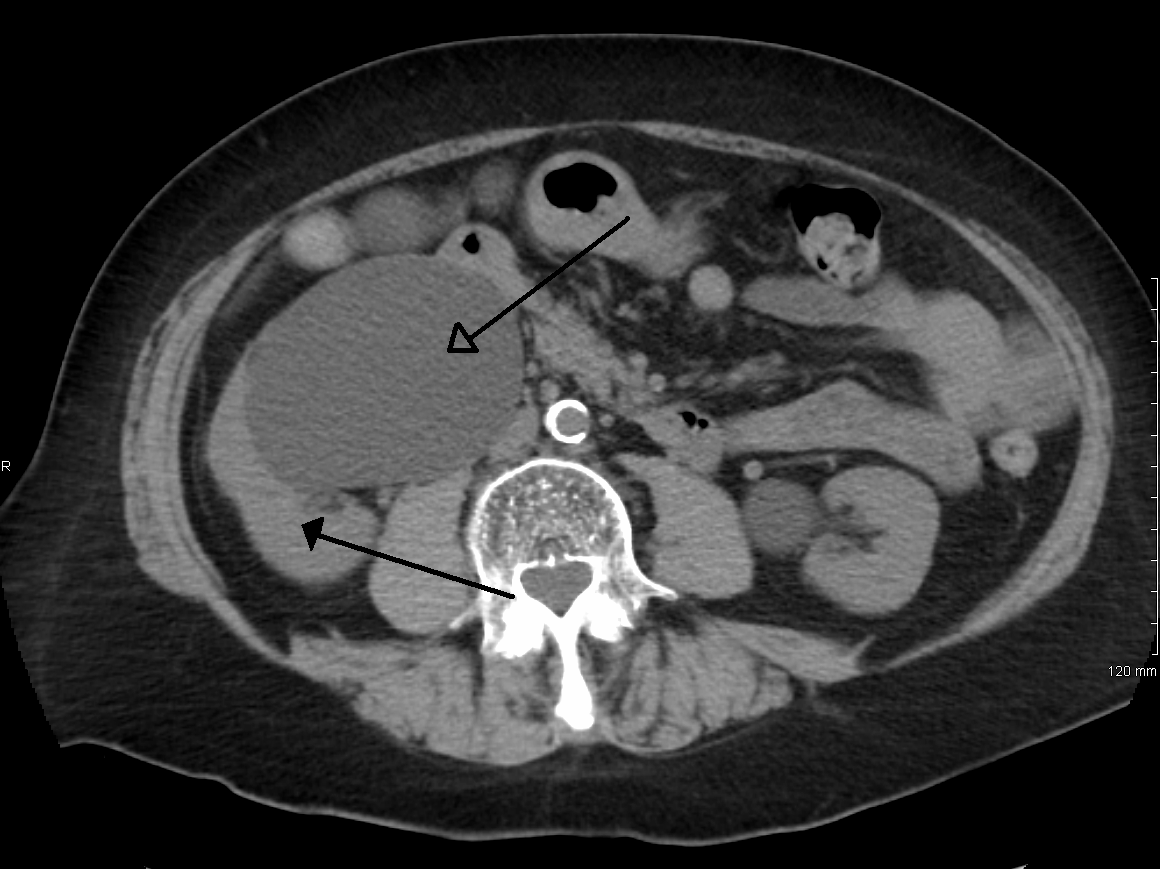

Интраренальная лоханка: рентгеновские снимки и примеры

Раздел: Фотоэссе